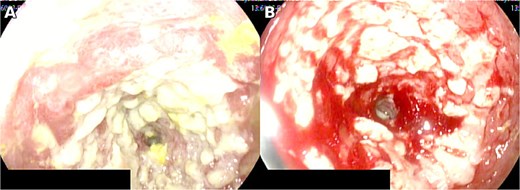

Initial laboratory testing showed leukocytosis of 12 000 per microliter with neutrophil predominance of 82%, creatinine 0.7 mg per deciliter, and liver function tests within normal limits. She had no relevant past medical history, denied corticosteroid use or other immunosuppressive therapy, and had a negative HIV test; therefore, she was considered immunocompetent. Contrast enhanced computed tomography demonstrated small bowel obstruction with two transition points in the proximal jejunum. Endoscopy revealed a circumferential jejunal ulcer larger than 5 cm with loss of vascular pattern, induration, whitish exudate, and contact bleeding (Fig. 1).

Circumferential jejunal ulcer measuring >5 cm, with loss of vascular pattern, induration, whitish exudate, and contact bleeding.

Clinical manifestations overlap with other causes of acute abdomen or obstruction; hence, 17 tissue diagnosis is required, demonstrating cytomegalic inclusions and positive IHC [2–4, 9]. In practice, IHC on tissue provides high specificity, whereas PCR may be complementary but can detect latent infection without proving tissue-invasive disease [4]. When the small bowel is involved, device-assisted enteroscopy enables targeted biopsies beyond the reach of standard endoscopy, thereby improving diagnostic yield [9]. In our patient, an extensive circumferential jejunal ulcer with stenosis, CT signs of obstruction, and lack of clinical improvement justified intestinal resection with anastomosis. Endoscopic patterns reported in immunocompetent individuals include irregular or circumferential ulcers with exudate and diffuse erythema, consistent with our findings [5]. In addition, imaging that demonstrates fixed transition points with proximal dilatation correlates with the need for operative management when clinical deterioration persists despite supportive care [6]. Concordance between imaging and intra-operative findings supported surgical planning, and histological confirmation guided antiviral therapy.